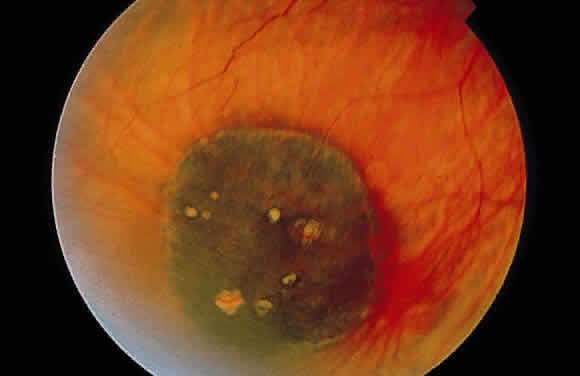

CONGENITAL HYPERTROPHY OF THE RETINAL PIGMENT EPITHELIUM

Congenital hypertrophy of the RPE occurs as a flat, round, usually hyperpigmented fundus lesion (Fig. 17). Often, a thin hypopigmented ring comprises the border of the abnormality. In contrast to inflammatory diseases, which produce RPE hyperplasia with rough edges, the margins of congenital hypertrophy of the RPE are well delineated (Fig. 18A). Commonly, depigmented lacunae can be seen within the confines of the lesion (see Fig. 17).

Fig. 17. Congenital hypertrophy of the retinal pigment epithelium. The flat lesion is essentially black with interspersed yellow-orange areas (lacunae) and has a well-circumscribed border. (Courtesy of Dr. Jerry Shields)

Histologically, congenital hypertrophy of the RPE is characterized by a monolayer of large RPE cells containing larger-than-normal pigment granules (Fig. 19; see Fig. 18B through E). Overlying photoreceptor elements have been shown to be degenerated, which explains the localized visual field defects corresponding to these areas.170

Congenital hypertrophy of the RPE usually is asymptomatic and is observed as an incidental finding on fundus examination. It has no malignant potential and should not be confused with choroidal nevi ormelanomas because congenital hypertrophy is flat, is usually black, and has sharp borders.